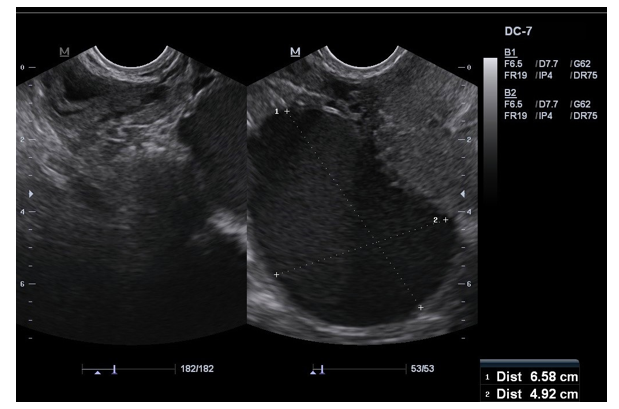

Ultrasound: Abdomen & Pelvis: Well-defined, solid masses in the myometrium with cystic degeneration Figure: 3 |

Patient E had enlarged uterus with multiple subserosal masses with free peritoneal fluid. The uterine mass biopsy showed spin-dle shaped smooth muscle cells suggestive of leiomyoma. Patient underwent total abdominal hysterectomy. There was complete res¬olution of symptoms in 3 weeks

Uterine leiomyoma is the benign tumor of uterine smooth mus-cle [11]. Patients usually present with dysmenorrhea, menorrhagia and abdominal distension [26]. An ultrasonography is the initial diagnostic tool for the confirmation of the diagnosis [11,26]. The current management strategies involve mainly surgical interven¬tions which include total hysterectomy versus partial myomecto-my depending on the patient’s age and her desire to preserve fer-tility [27]. In this case series patient E is a 38-year-old female who had completed her family with four children, she presented with menorrhagia and abdominal distension. Uterine leiomyoma was noted on the ultrasound imaging.(Figure:3) As she did not desire any further children she opted for total abdominal hysterectomy.

Figure 2: Anterior Wall Leiomyoma